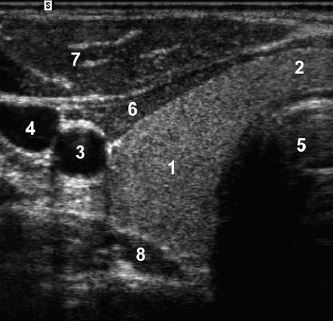

A

1. rotator cuff

2. cartilage

3. humeral head

4. anatomic neck

5. greater tuberosity

6. subdeltoid bursa

7. deltoid muscle

8. biceps tendon

The intra-articular portion of the biceps tendon

separates the subscapularis and the supraspinatus.